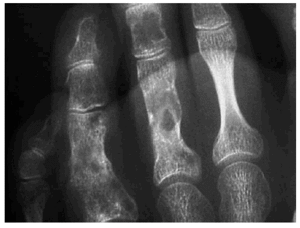

En el estudio radiológico realizado se observaban, junto a secuelas de antiguas fracturas, múltiples lesiones constituidas por imágenes radiolúcidas, a veces con borde escleroso o desflecado, localizadas a nivel de la parrilla costal, húmero, cúbito, radio, sacro, fémur, tibia, peroné, así como huesos de tarso, carpo y falanges. Dichas lesiones eran sugestivas de encondromatosis múltiple (fig. 2) que en algunos lugares coincidían con la localización de los hemangiomas.

Fig. 2.--Encondromas óseos.